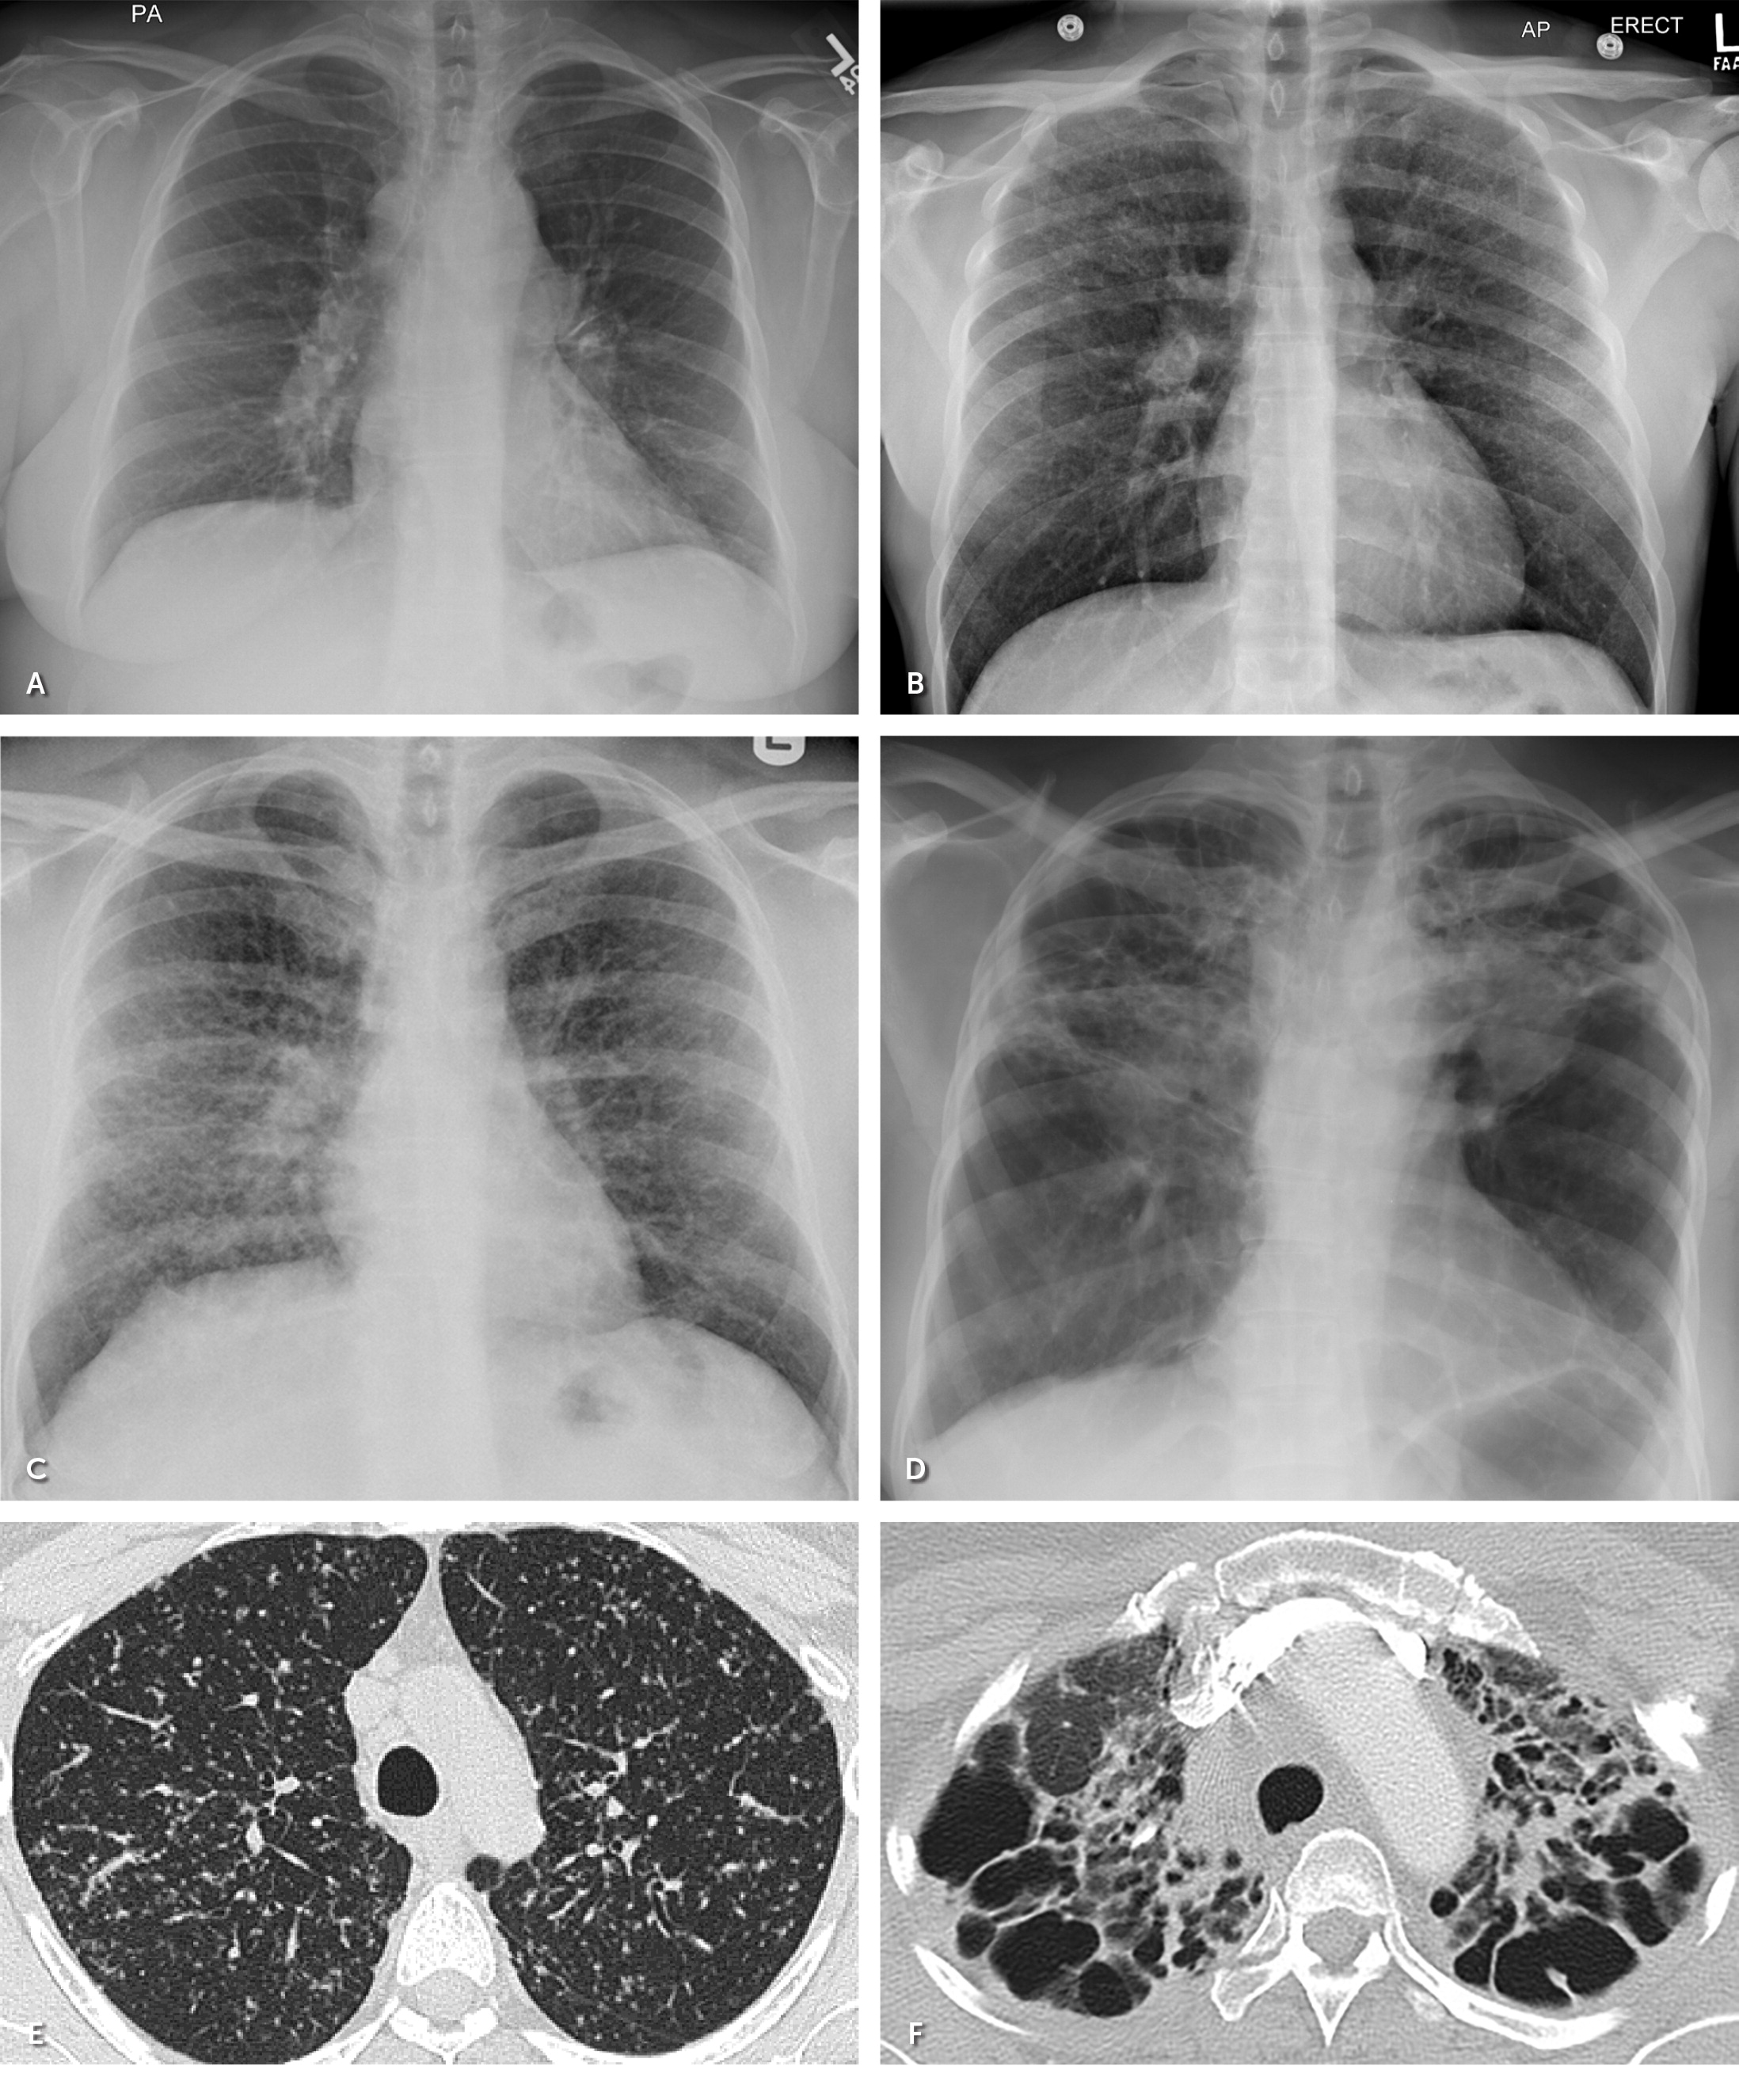

Approximately 80% to 90% of patients with biopsy-confirmed pulmonary sarcoidosis have abnormalities on radiography, most commonly bilateral hilar lymphadenopathy.24,27 The Scadding staging system was developed based on chest radiographic features for prognostic purposes 23,32,33 (Figure 3). High-resolution CT typically shows upper lobe lymphatic and peribronchovascular nodules and subcarinal and hilar lymphadenopathy.23,24 Unlike chest radiography, high-resolution CT closely inspects lung parenchyma to aid in quantifying lung fibrosis, which can affect treatment decisions and prognosis. High-resolution CT can identify the best peripheral lymph nodes for tissue sampling if a diagnosis is uncertain.23,27

FIGURE 3.

Radiographic Scadding staging of sarcoidosis. (A) Stage I: chest radiograph with bilateral hilar and mediastinal lymphadenopathy. (B) Stage II: chest radiograph with parenchymal involvement and bilateral hilar lymphadenopathy. (C) Stage III: chest radiograph with midlung predominant reticulonodular opacities. (D) Stage IV: chest radiograph with hilar distortion and elevation, with upper lobe–predominant fibrosis. (E) High-resolution chest computed tomography of stage III sarcoidosis with predominantly perilymphatic micronodules. (F) Computed tomography showing stage IV fibrosis.

Pulmonary function testing has normal findings in approximately 80% of patients without parenchymal infiltrates on imaging.27 Abnormal pulmonary function test patterns vary in sarcoidosis, depending on the distribution of airway inflammation, and include obstructive (commonly found in fibrotic disease), decreased diffusing capacity, and restrictive.23,24,34